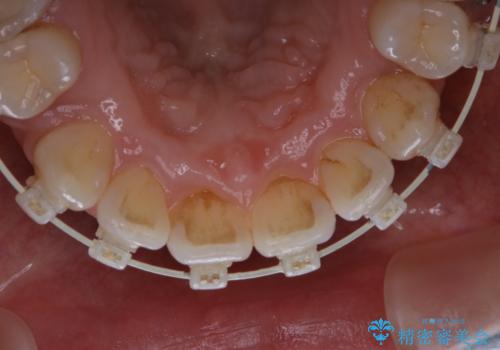

ワイヤー矯正中のPMTC

- ワイヤー矯正中に装置の周りの着色が気になるとのことで来院されました。PMTC30分コースを行いました。

ワイヤー矯正中も、歯の表面に着色(ステイン)が付着することがあります。着色(ステイン)が付着したままだと審美的な問題以外にも、虫歯を発見しずらいことや、細菌が繫殖しやすくなることがあります。クリーニングを行うことで、虫歯や歯周病予防に効果的だったり、もちろん見た目も審美的です。クリーニング後には、汚れが取り除かれ、お口の中がスッキリ・爽快感で気持ちがよくなります。矯正中も定期的にPMTCを行うことが大切です。